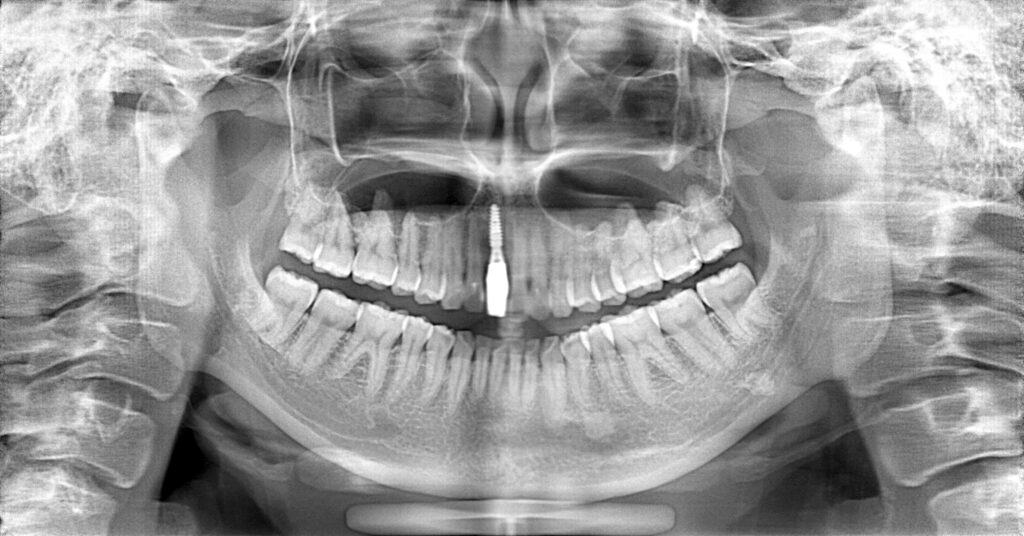

症例一覧 インプラント症例2 2024.11.25 治療内容インプラント主訴前歯事故で折れたのでインプラント治療を行いたい費用¥946,000(1本)治療期間7ヶ月 インプラント症例3 前の記事 インプラント症例1 次の記事